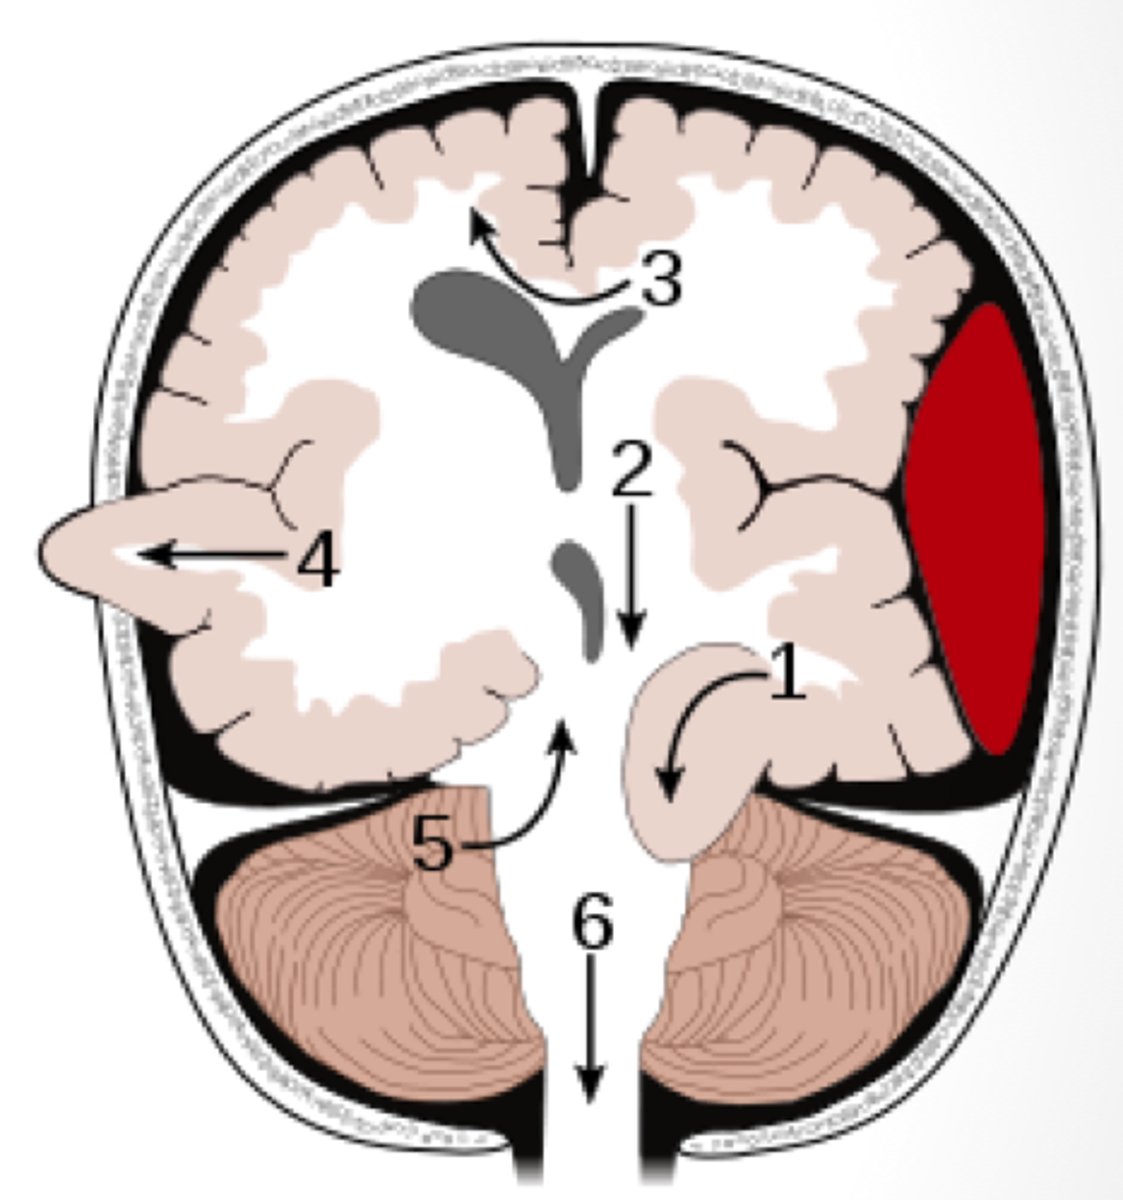

brain herniation

displacement of brain tissue to due increased ICP

subfalcine (cingulate) herniation

herniation of the brain where the medial frontal lobe shifts under the falx cerebri

transtentorial (uncal) herniation

herniation of the brain where the temporal lobe shifts through the tentorial notch

*1 on diagram

tonsillar herniation

herniation of the brain where cerebellar tonsils descend through the foramen magnum

central herniation

herniation of the brain where there is downward displacement of the brainstem

presentation of what impairment/issues with what cranial structure?

- altered consciousness

- pupillary asymmetry or non-reactive pupils

- abnormal posture

- respiratory and CV instability